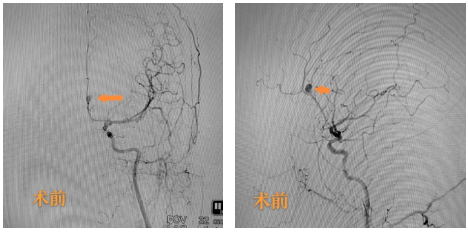

术前造影提示左侧大脑前动脉动脉瘤

术后造影提示动脉瘤完全致密栓塞,载瘤血管通畅

紧急完善术前检查后,纪文军主任医师团队为马女士急诊行全脑血管造影术。术中确诊左侧大脑前动脉瘤。纪文军主任医师紧急主持召开术前讨论,患者动脉瘤位于胼胝体旁大脑前动脉A3段,瘤颈较窄,考虑患者为年轻女性,血管通路好,适合介入栓塞治疗,决定为她行介入栓塞治疗。制定好手术方案后,由纪文军主任医师主刀,在罗有才副主任医师、李涛副主任医师、赵乐副主任医师的配合下,患者动脉瘤得以致密栓塞,载瘤动脉通畅、血流完全不受影响,患者颅内炸弹被精准拆除。为引流颅内出血,由罗有才副主任医师主刀、李涛副主任医师配合下再给患者行侧脑室穿刺引流术,手术顺利,术后患者返回神经外科二病区重症病房。